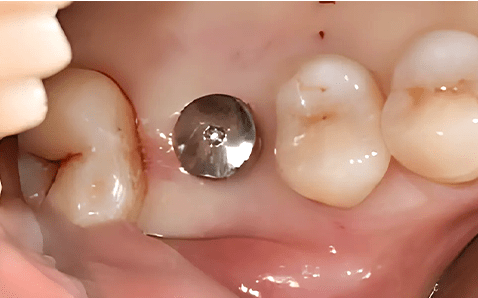

Case 02

Before Implant Placement Right After Flapless Implant Placement

Photo Date : 2024.06.19